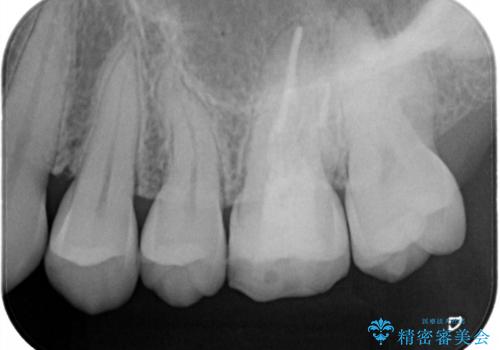

海外転勤が決まり、急いでセラミック治療をしてほしいとご来院された患者様です。

根管治療に症状がなく、上の歯に関しては土台もそのまま使用可能であったため、下の歯の土台、上下の歯のセラミック治療を行いました。

今回は幸い、症状がなく、根管治療の再治療が必要でないため、円滑に治療を進めることができました。